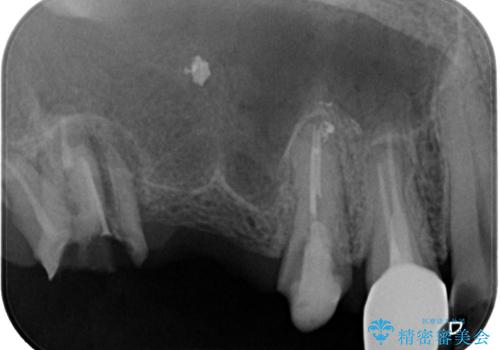

- 土台の歯が割れてしまって、歯がグラグラしているとのことで来院された患者様です。

いずれの歯も抜歯が必要な状態であり、抜歯即時埋入によるインプラント治療を行うこととしました。

右上奥歯は骨欠損の範囲が広いため、抜歯即時埋入は可能であっても、即日で仮歯を装着する即時荷重は難しいと判断されたため、手前の歯まで仮歯を装着することとしました。

術後にインプラントの安定値を測定し、十分な値が達成された後、速やかにセラミッククラウンにて補綴治療を行うこととしました。

強い咬合力により歯根破折を繰り返しているため、即日荷重あるいは早期荷重による他の歯への負担を軽減することが重要となります。

抜歯即時埋入インプラントは、咬合力によるトラブルを回避する、非常に有用な手段となります。